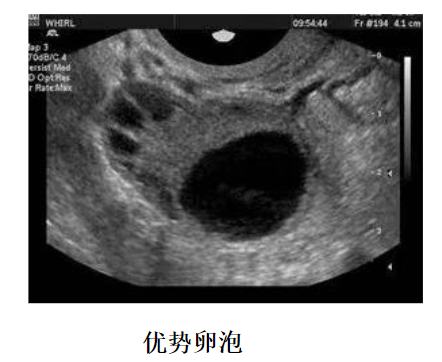

2、时间把握,在月经周期较长的患者进行卵泡监测的时候,建议从月经周期第10天开始,如果期间有发现12mm以上的卵泡,则需要每天监测一次,如果并没有发现什么优势卵泡,可以3天监测一次。

A:如果卵泡监测到卵泡大小在12mm以下的时候,三天一次,当监测到卵泡大小为12mm以上的时候,建议一天监测一次,当卵泡趋近成熟的时候,可能需要一天监测两次,如果一直没有监测到卵泡,也是三天一次,后面根据卵泡数量进行跟进,一直监测到卵泡成熟为止。